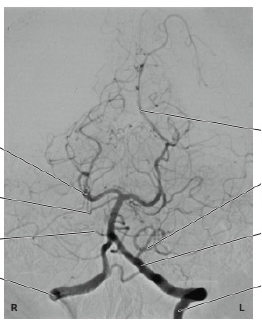

22

ID the vessels